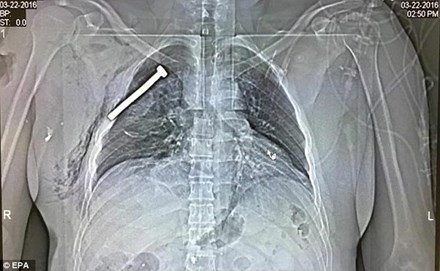

Ảnh X-quang chụp phổi của một nạn nhân sống sót sau vụ khủng bố hôm 22/3. Ảnh: EPA

Hãy xem bức hình chụp X-quang phổi của một nạn nhân bị thương nhưng may mắn sống sót trong vụ khủng bố xảy ra tại sân bay Zaventem (thủ đô Brussels, Bỉ) hôm 22/3 vừa qua mới thấy khủng khiếp.

Sau khi vụ khủng bố xảy ra, nạn nhân này đã được đưa đến bệnh viện quân đội ở Neder-over-Heembeek, phía bắc thủ đô Brussels.

Qua hình ảnh, có thể thấy trong phổi của nạn nhân bị găm một chiếc đinh có chiều dài khoảng 3 inch (tương đương 7,6 cm). Vị trí của chiếc đinh chỉ cách trái tim của nạn nhân vài cm.